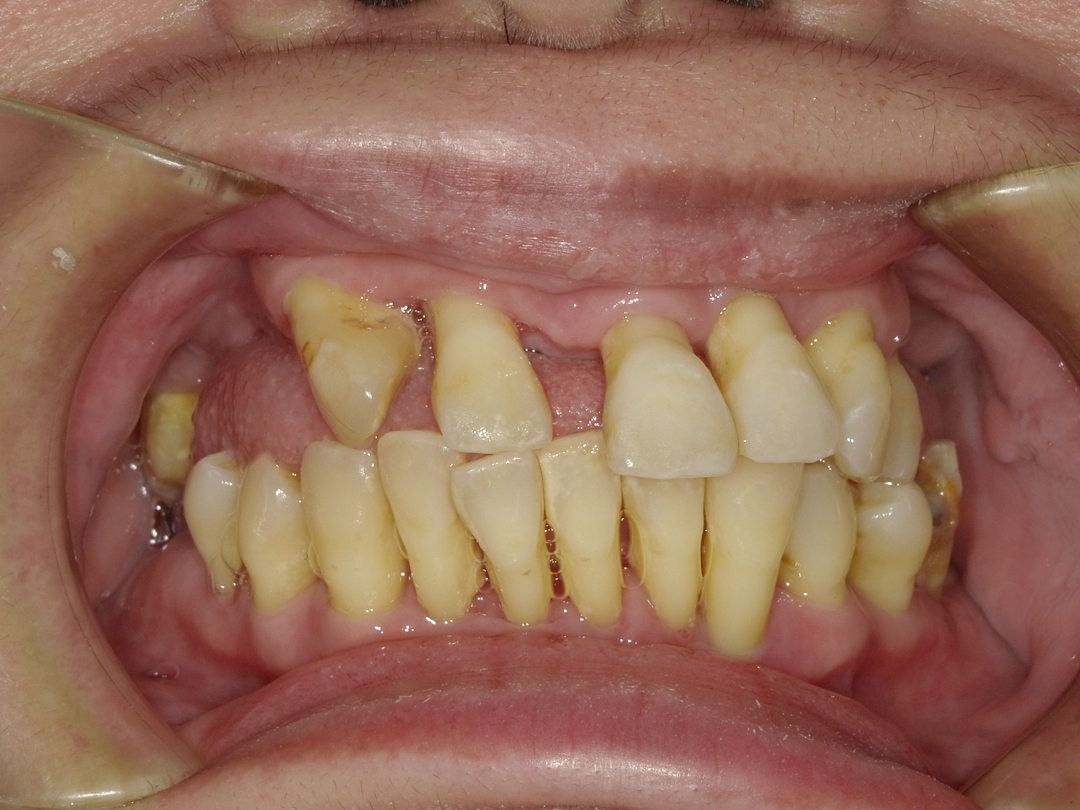

ALL ON全口重建

術式介紹

ALL ON全口重建是由4-6 顆植體(依條件而定)成,專為多顆缺牙或全口無牙患者設計的創新全口重建技術,僅需4-6 支植體即可支撐一整排固定式假牙,大幅減少手術次數與成本,並縮短療程時間。

適用無牙或重度牙周病患者

免補骨/少補骨即可植牙,降低手術複雜度